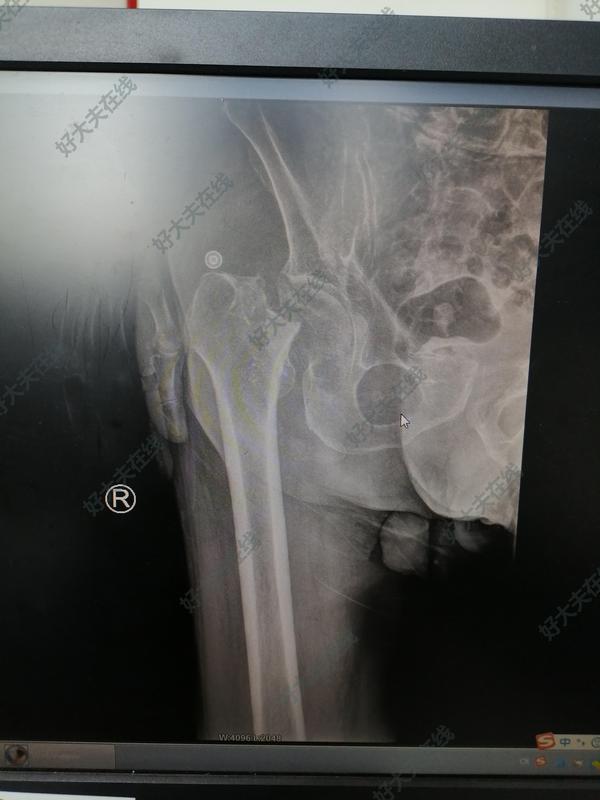

治療前88歲高齡患者,摔傷致左髖部疼痛伴活動受限2小時入院,急診拍片顯示:左側股骨轉子間骨折治療中完善術前檢查,多學科會診,入院第三天行椎管麻醉下左側股骨近端髓內釘內固定術(PFNA)治療后治療后7天術后疼痛緩解,患者可扶助行器行走